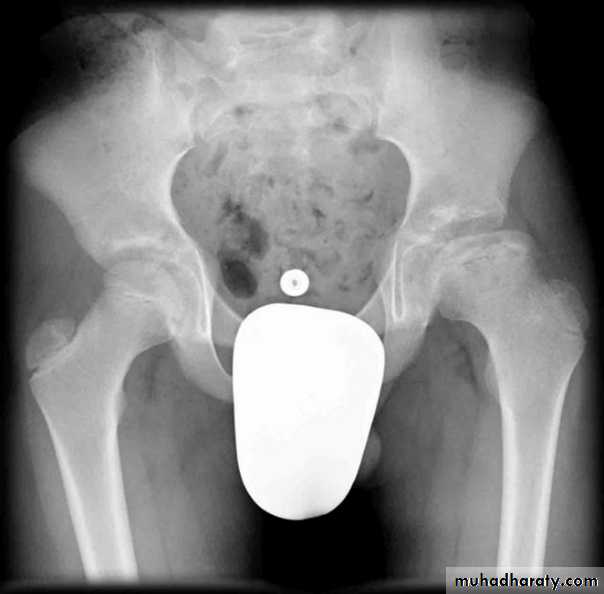

*Triradiate pelvis in which pelvic side walls bend inward (sever cases of osteomalasia )

Who can you do Von Rosen view

At 3-6 months :abduction of the thigh 45 degree and internal rotation

Shenton line is drawn along the inferior border of the superior pubic ramus and should continue laterally along the infero medial aspect of the proximal femur as a smooth line. If there is supero lateral migration of the proximal femur due to DDH then this line will be discontinuousPerkin line is drawn intersecting the lateral most aspect of the acetabuler roof & iliac creast

Q…CDH occurs most commonly in ????(70%) in the left hip . Bilateral involvement is seen in 5%

Q…By simple diagram draw pelvis with lines (shenton’s & Perkins line)